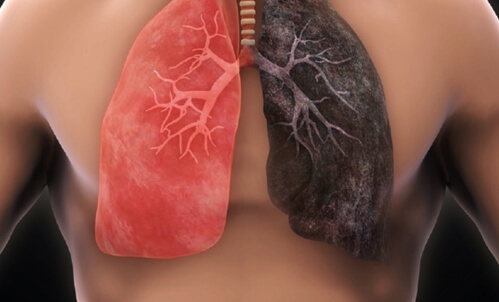

먼저 국가 폐암 검진이 왜 도입됐는지부터 설명을 드리겠습니다. 우선 많은 분들이 이미 알고 계시지만, 폐암의 약 90%는 흡연이 원인입니다.

담배를 피우는 흡연자는 비흡연자에 비해 폐암 발생 위험도가 약 11배 정도 높습니다. 그렇기 때문에 오랫동안 흡연을 하신 분들은 반드시 조기 폐암 검진이 필수적입니다.

이렇게 위험한 폐암의 데이터를 살펴보겠습니다. 주요암의 5년 상대 생존율을 살펴보면 췌장암이 가장 낮은 생존율을 보이며, 그다음으로 낮은 생존율을 보이는 암이 바로 폐암입니다. 생존할 확률이 낮은 쪽에서 2등이라는 것은 굉장히 위험한 암이라는 것입니다. 그런데 췌장암보다는 폐암 발병률이 더 높기 때문에 췌장암보다 더 많은 사망자를 발생시킵니다.

이러한 폐암은 누구나 알다시피 흡연과 굉장히 밀접한 통계를 가지고 있습니다. oecd 흡연 관련 통계를 비교하면 대한민국의 흡연율은 oecd 평균보다 높습니다. 특히 남성분들의 흡연율이 oecd 평균에 비해서 약 60% 정도가 더 많습니다. 그렇기 때문에 국가에서 장기 흡연자들을 대상으로 폐암 검진 사업을 시작하게 된 것입니다.